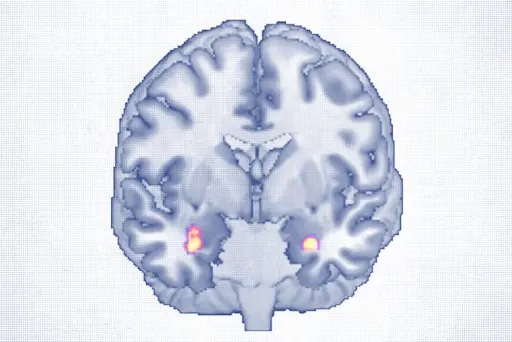

この薬は、研究で自閉症の子供の70%以上にみられるとされる脳の栄養不足に働きかけるものです。

2002年、彼らのチームは、出生前・出生後に葉酸補給を受けていたにもかかわらず、影響を受けた赤ちゃんの脳に深刻な葉酸欠乏があることを発見しました。脊髄液を調べると、ビタミンの活性型が著しく低いことがわかりました。

脳葉酸欠乏症の多くの子供は、脳の主要な葉酸レセプターに対する自己抗体を持っていることが判明しました。これらの自己抗体が葉酸レセプターをブロックし、食事や補給からの通常の葉酸吸収を実質的に妨げてしまうのです。

2013年、リチャード・フライ博士が主導し、クアドロス氏と共同で行われた研究で、クリニックに通う自閉症の子供の75%以上が、脳への葉酸取り込みを阻害する自己抗体を持っていることが判明しました。

ロイコボリンは、通常とは異なる経路で脳に入るため、自己抗体のブロックを回避でき、これらの子供にとって有効な治療法であることが示されました。

脳の葉酸不足を補うことは、神経学的に大きなメリットがあります。葉酸は神経伝達物質の生成や神経の健康維持のためのDNAの形成・修復、さらに神経信号を速めるミエリン鞘の形成を助けます。